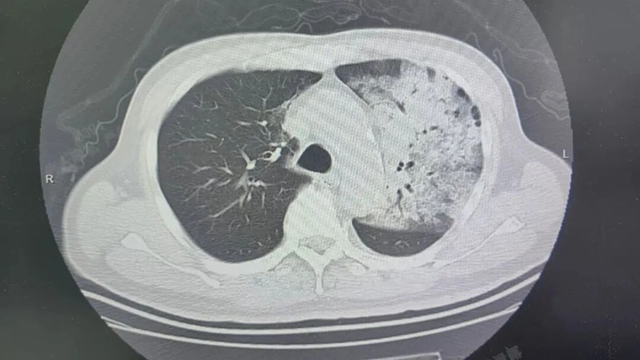

Sau khoảng một tuần điều trị tại bệnh viện địa phương, bệnh tình của ông đột ngột xấu đi. Bệnh nhân bắt đầu khó thở, rối loạn ý thức. K ết quả chụp CT cho thấy 2 phổi bị nhiễm trùng nặng, gần như “trắng xóa” . Dù đã được hỗ trợ thở máy nhưng tình trạng oxy máu vẫn không cải thiện.